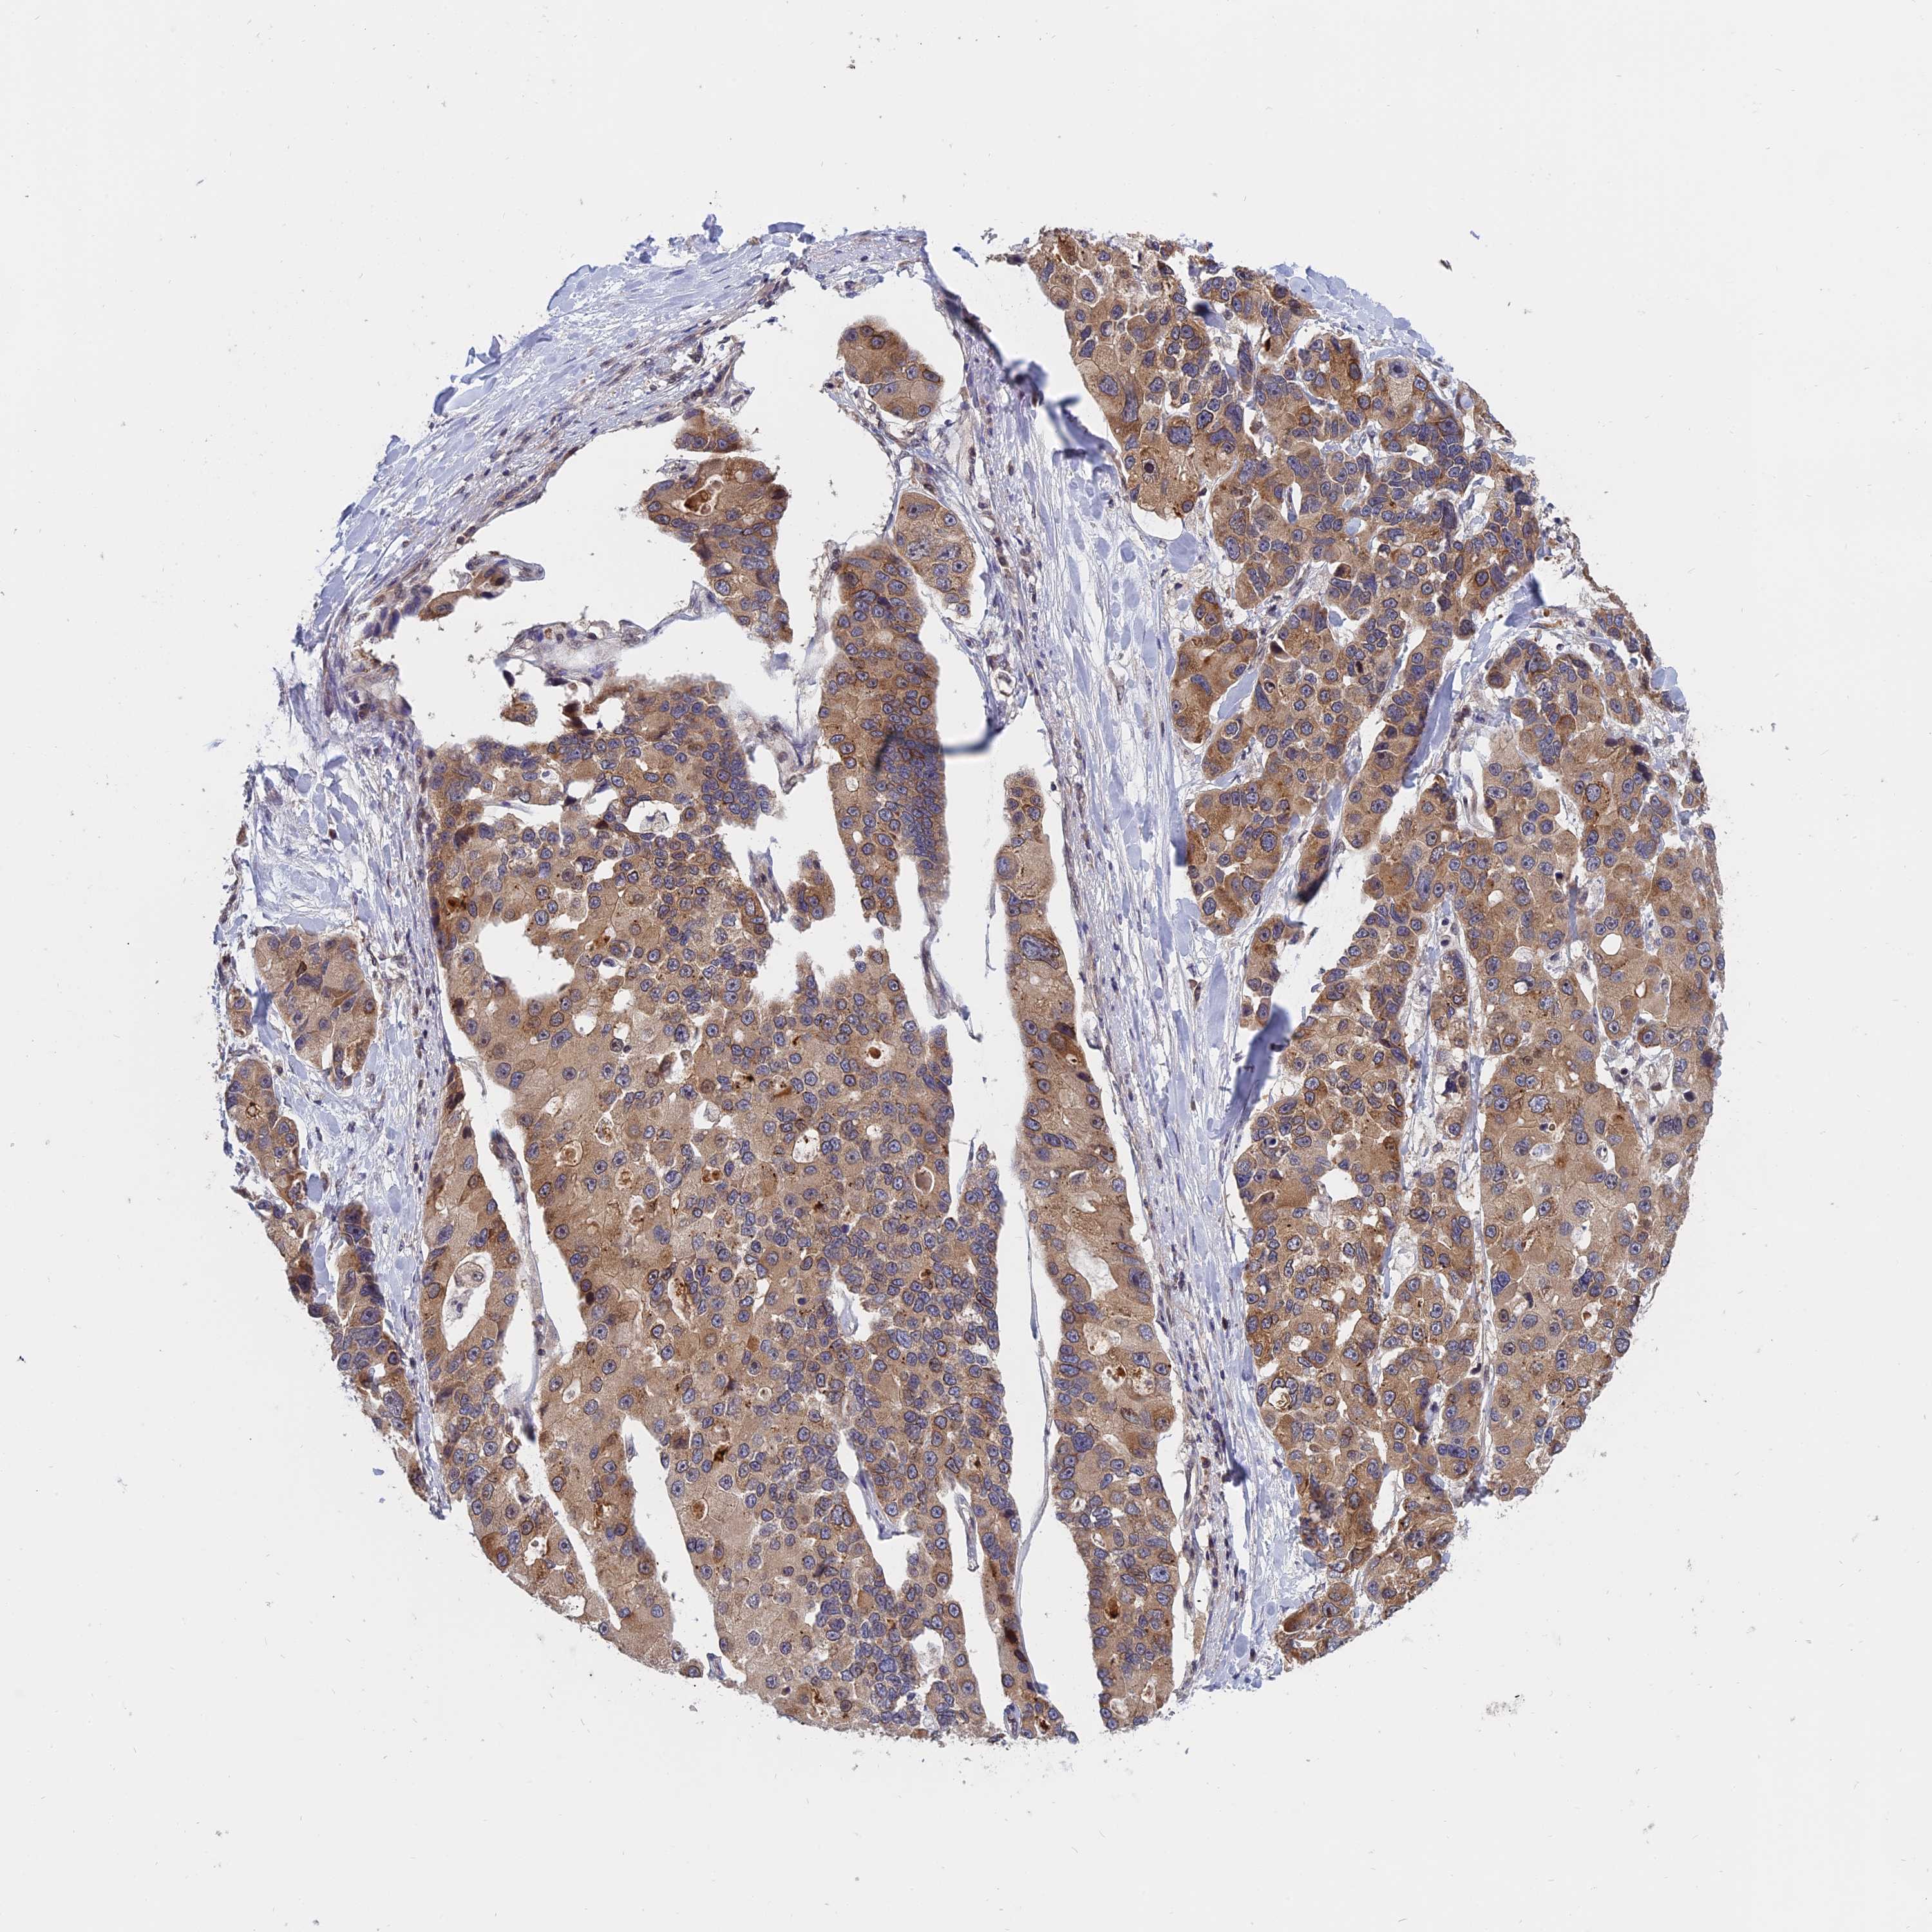

CANCER LUNG CANCER Show tissue menu

LUAD TCGA LUAD VALIDATION LUSC TCGA LUSC VALIDATION PROTEIN LUAD CPTAC PROTEIN LUSC CPTAC PROTEIN EXPRESSION

ANTIBODIES

AND

VALIDATION